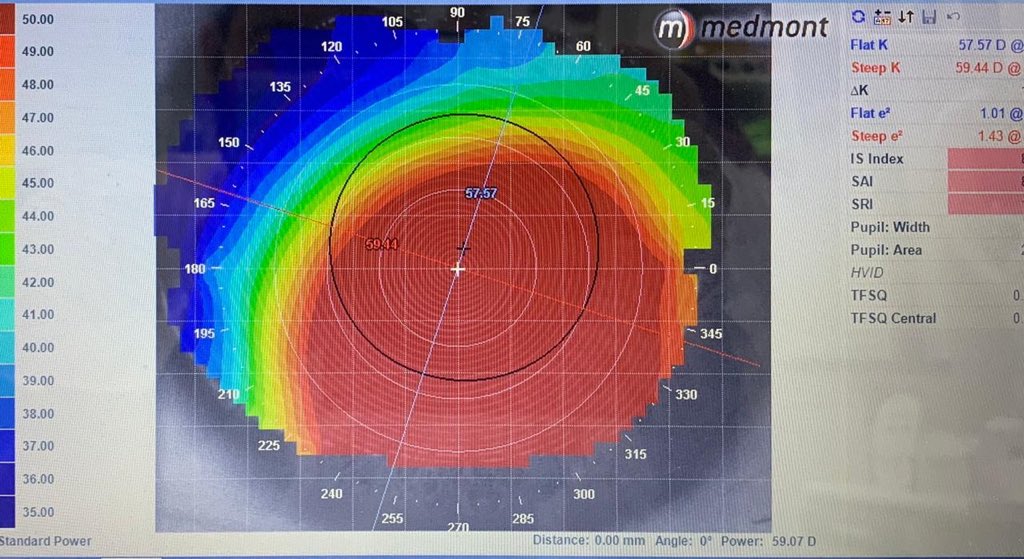

عمر المريض 32 سنه ، زار العياده قبل 4 سنوات ، معه قرنيه مخروطيه متقدمه ولكن من النوع الي نسميه Keratoglobus اي ان القرنيه محدبه ومخروطيه ولكن بشكل منتظم ، ينتج عنه قصر نظر شديد وانحراف قليل عكس حالات القرنيه المخروطيه التقليديه حيث يزيد الانحراف عن القصر في معظم الاحيان !!

في زيارته الاولى قبل 4 سنوات ، كان يستخدم عدسات لينه تقليديه قوتها تقريبا -10.00 درجات ، طبعا كونها اصلا غير ملائمه لسطح القرنيه المحدب كانت تتحرك كثير وتسبب جفاف والم واحمرار وكراهيه شديده للضوء ولكن كان يتحمل كل هالمعاناه لانها تعطيه نظر يقدر يمشي حاله فيه !!